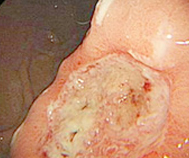

• 无痛胃镜

• 无痛肠镜